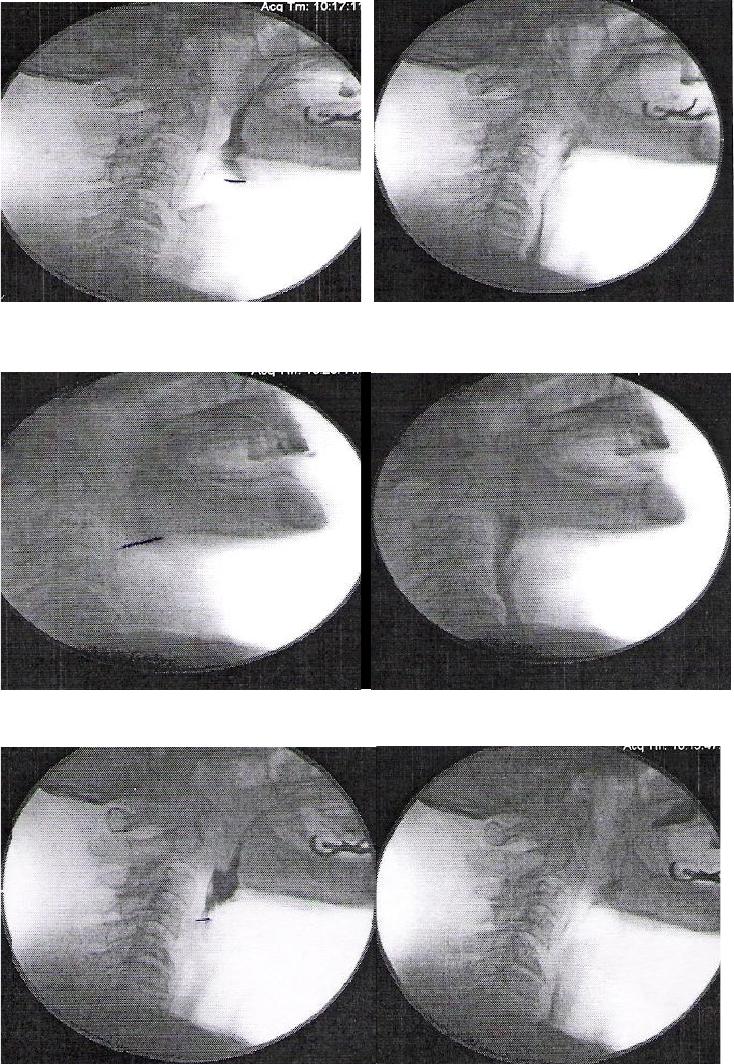

ANEXO E Imagens videofluoroscópicas da deglutição, registrando

escape prematuro e reação de deglutição atrasada, p e s

crioestimulação, com líquido e pastoso.........................................................